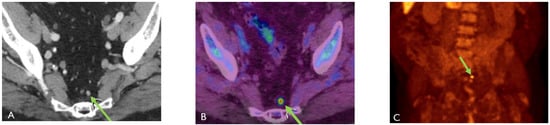

Detection of Loco-Regional Disease and Distant Metastases